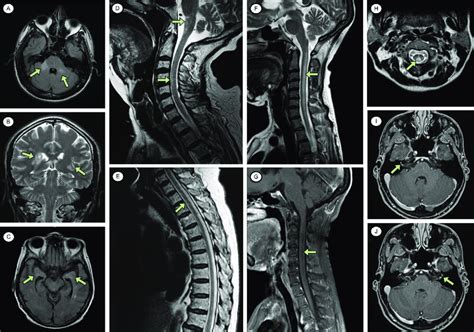

Hey guys! Ever wondered what happens when your brain gets a little… off ? Well, when doctors suspect something’s amiss in your central nervous system (CNS) – that’s your brain and spinal cord, for those keeping score – they often turn to diagnostic imaging. This can involve a variety of techniques, such as MRI (magnetic resonance imaging), CT scans (computed tomography), and even ultrasounds. These methods allow them to peer inside and see what’s going on. But what exactly are they looking for? And what do those “other abnormal findings” actually mean ? Let’s dive in and explore some of the common things that can pop up on these scans, shall we?

On imaging, tumors can appear as masses with varying characteristics depending on their type and aggressiveness. They may show up as bright or dark spots on MRI, and they can sometimes cause swelling or displacement of surrounding brain structures.

• Ischemic Stroke: In this case, there’s a blockage, leading to brain tissue death. On an MRI, early signs might include subtle changes in the affected areas. CT scans can also detect ischemic strokes, especially after several hours.

• Hemorrhagic Stroke: This involves bleeding in the brain. CT scans are particularly good at detecting bleeding, which appears bright on the images. The location and extent of the bleeding help determine the severity and the best course of treatment.

• Meningitis: Inflammation of the meninges, often caused by bacteria or viruses. Imaging can reveal swelling and enhancement of the meninges.

• Encephalitis: Inflammation of the brain itself. This can be caused by viruses (such as herpes simplex) or other infections. MRI can show areas of inflammation and damage.

• Abscesses: Collections of pus in the brain. These typically appear as round masses with a thick wall on imaging.

Demyelinating diseases damage the myelin sheath, which is the protective covering around nerve fibers. Multiple sclerosis (MS) is the most well-known of these. On MRI, MS often appears as multiple areas of inflammation and damage in the brain and spinal cord. These lesions can vary in size and location.